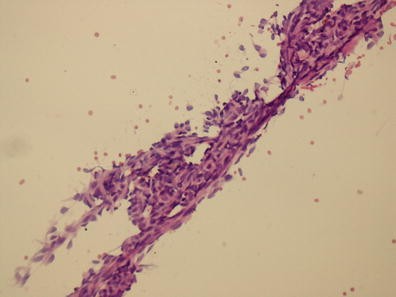

Objective: To identify mutational biomarkers using next-generation sequencing (NGS) and endoscopic samples for stratification of Barrett Esophagus (BE) patients at increased risk of dysplasia.

Method: Ion Torrent AmpliSeq Cancer Panel was used to screen for mutations in 46 cancer genes. Sixteen samples were tested: Intestinal metaplasia from 6 patients (IM-P) with concomitant high-grade dysplasia (HGD)/adenocarcinoma (EAC) and HGD/EAC in 3 patients; IM of 7 patients followed for at least 2 years without any dysplasia (IM-N). Ion torrent suite software and ANNOVAR were used for analysis.

Results: The most frequent mutations in IM and HGD/EAC were detected in TP53 spanning codons 150 to 280. Four of 6 IM-P patients had TP53 mutations in IM samples and in HGD/EAC tested. None of the 7 IM-N patients had TP53 mutations. Sensitivity of TP53 mutation for presence of concomitant dysplasia was 67 % and specificity was 100 %.

Conclusion: DNA from routine endoscopic samples can be efficiently used to simultaneously detect multiple mutations by NGS. TP53 mutations were frequently detected in IM of patients with HGD/EAC but not in patients who did not progress to HGD/EAC, suggesting that TP53 mutational testing may be useful to identify IM-P patients who may benefit from closer surveillance.